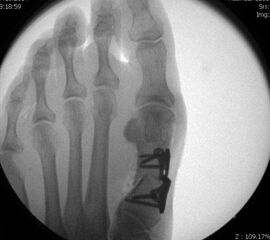

Nach Bestimmung der korrekten Osteotomiehöhe wird mit dem MIS-Mikrotom eine je nach Seitendominanz des Operateurs dorsolaterale oder dorsomediale 3-4mm lange Längsinzision parallel zu den Strecksehnen auf Höhe des metadiaphysären Überganges am distalen, zu osteotomierenden Metatarsale  durchgeführt. Im Anschluss erfolgt die Präparation mit einer schlanken, im Schaft gebogenen und vorne stumpfen Raspel oder mit einem gebogenen Klemmchen. Die Präparation erfolgt unter stetigem  Knochenkontakt mit der Kortikalis des Metatarsale medial oder lateral bis nach plantar unter die Beugesehenen.  So kann der Weg für die Fräse vorpräpariert und eine Weichteilinterposition zwischen Fräse und Knochen vermieden  werden.

Jetzt erfolgt das Einbringen der Fräse im 45°-Winkel von distal dorsal nach proximal plantar. Auf steten Knochenkontakt mit der Kortikalis zur Vermeidung eines Weichteilinterponates sollte geachtet werden. In unserer Abteilung erfolgt vor Beginn der Osteotomie nun eine nochmalige Lagekontrolle der Fräse unter dem Bildwandler im dorsoplantaren Strahlengang. Eine zusätzliche laterale Aufnahme kann die Tiefe der eingebrachten Fräse in Bezug auf das zu osteomierende Metatarsale zeigen, ebenso ermöglicht sie eine Kontrolle des 45°-Winkels.

In einer rotatorischen Bewegung mit dem Drehpunkt im Bereich der Hautinzision erfolgt nun die Osteotomie zunächst - in Abhängigkeit von der zu operierenden Seite und der Rechts- oder Linkshändigkeit des Operateurs  - des medialen bzw. lateralen Kortex des Metatarsale, gefolgt von den plantaren Anteilen und anschliessend dem gegenseitigen Kortex. Am Ende der rotatorischen Bewegung befindet sich die Fräse, die am Anfang der Osteotomie noch parallel zum Metatarsaleschaft ausgerichtet war, im 90°-Winkel zu diesem.

Mit dem plantar unter dem Metatarsaleköpfchen aufliegenden Zeigefinger der Gegenhand kann die Vollständigkeit der  Osteotomie durch ein Nachlassen der Widerstandes unter dem Köpfchen palpiert werden. Falls nötig, kann dies auch durch Zug an der Zehe unter Bildwandler zusätzlich bestätigt werden. Das Metatarsaleköpfchen wandert durch die Osteotomie von allein um einige mm nach proximal und dorsal.  Eine zusätzliche manuelle Verkürzung des Metatarsale ist aus biomechanischen Gründen zu vermeiden.